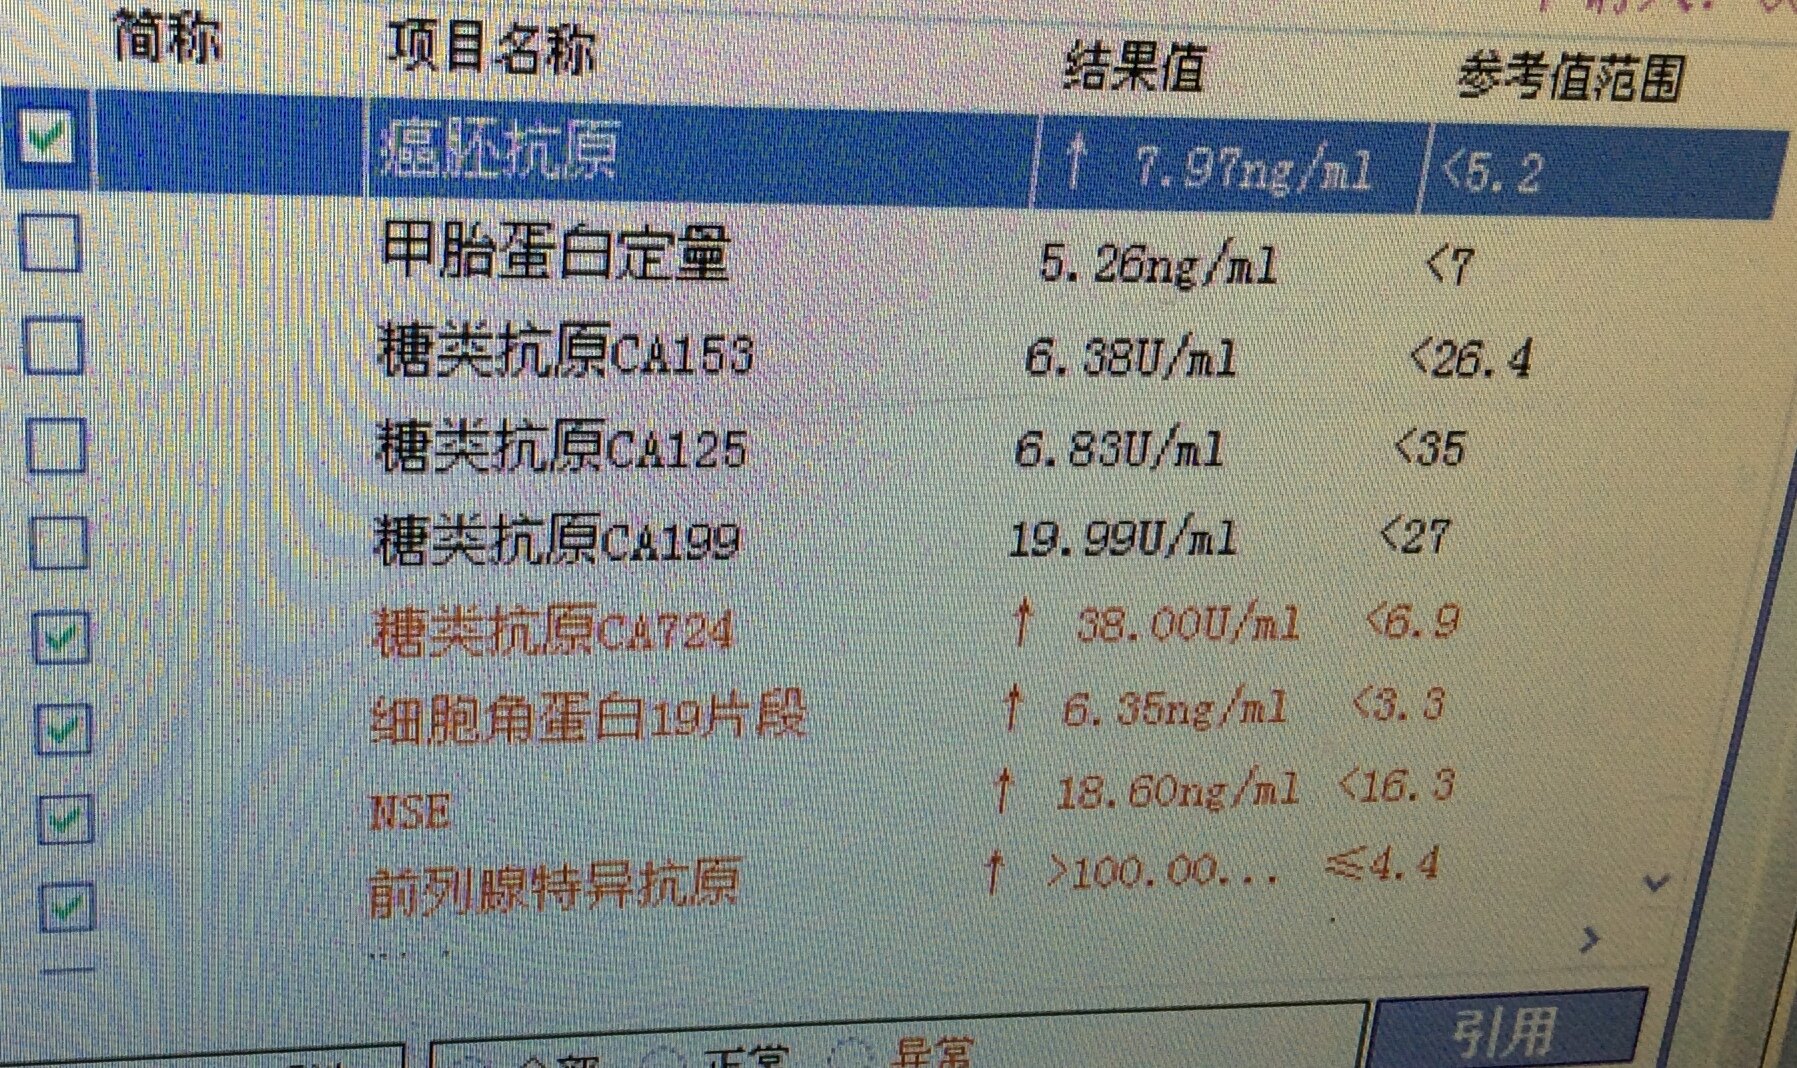

上述免疫组化结果辅助诊断为前列腺腺泡腺癌累及直肠。

加上上述实验室检查,血清psa升高显著,前列腺腺泡腺癌累及直肠就确诊了。所以,老年男性,直肠占位,不能忽视前列腺癌累犯。上述案例,也一再显示癌的发生发展,很长时间内都是静悄悄的,癌可以逃逸人体免疫系统的监控,而疯狂的无序无节制生长,直到破坏了关键器官或组织,才会引起相应的症状。为此,中老年人,规范的健康体检,规范的肿瘤筛查和血清肿瘤标记物的检测,都是十分必要的。当然,我们自己对自己健康的关注才更加重要。了解自己的身体,关注自己的健康,增加健康常识和健康意识都是重要和必需的。